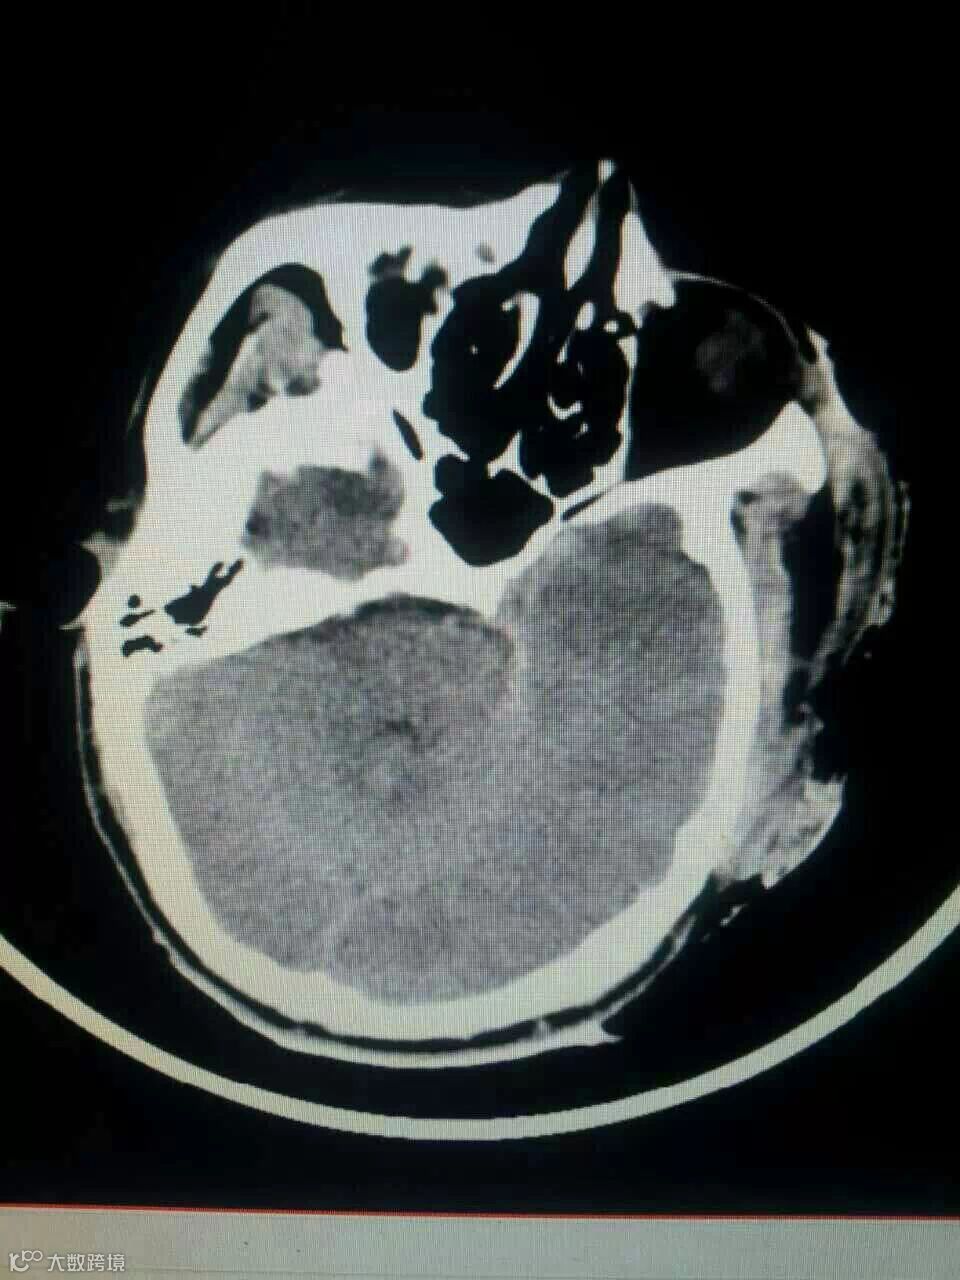

中国人民大学法学院12级法律硕士杨勇(学号2012100423)之父于2015年5月14日在湖南株洲攸县驾驶摩托车被货运卡车拖倒撞伤,经诊断为颅内严重损伤,时至今日尚未清醒,肇事司机无力支付医药费,杨勇同学亦已倾尽所有。